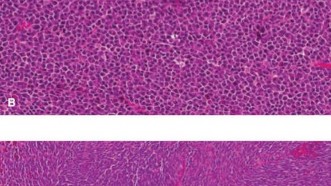

Ewing sarcoma (ES) is a highly aggressive, malignant small round blue cell tumor of bone and soft tissue, belonging to the Ewing sarcoma family of tumors (ESFT). It is characterized by specific chromosomal translocations, most commonly t(11;22)(q24;q12), resulting in the EWS-FLI1 fusion gene, which serves as a molecular hallmark and drives its oncogenesis.

- Histopathological examination, including immunohistochemistry (CD99, NKX2.2) and molecular genetics (EWS-FLI1 fusion), confirms diagnosis and assesses tumor response to neoadjuvant chemotherapy (tumor necrosis percentage), which is a key prognostic indicator.